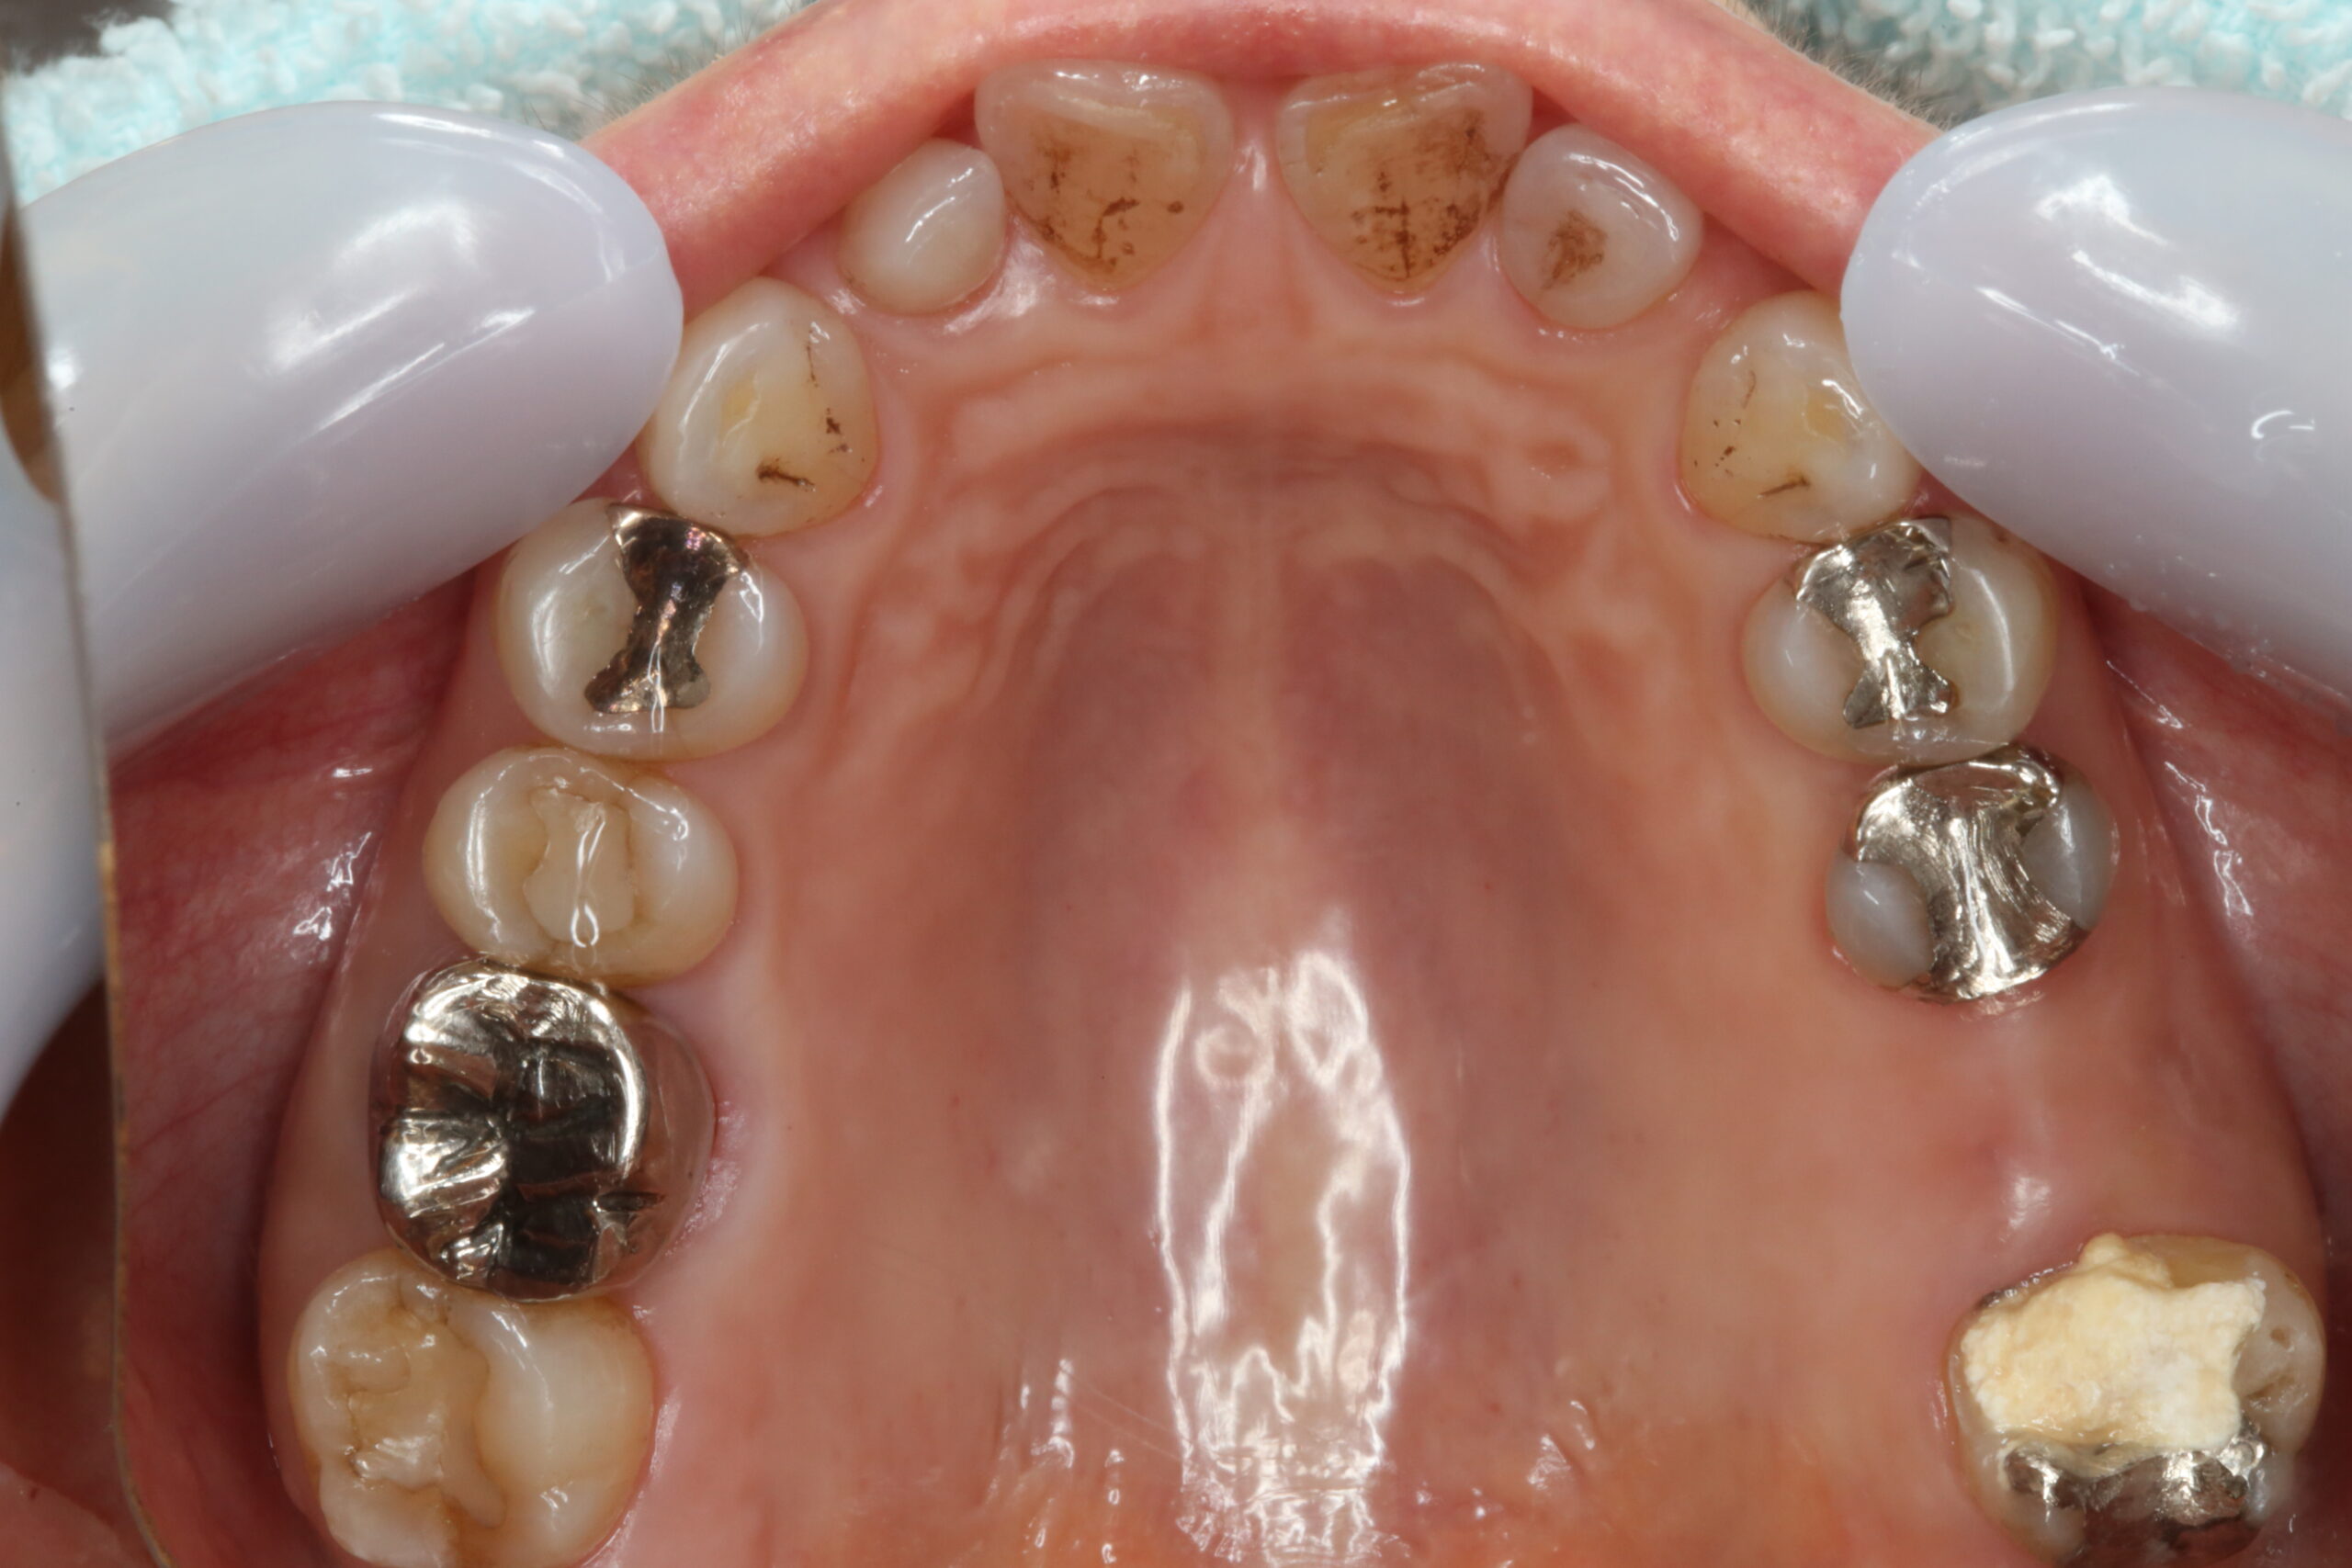

写真右下に写っている大臼歯の根管治療を行うことになりました。